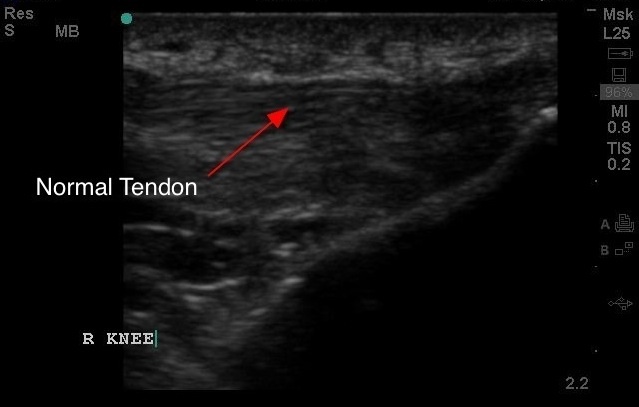

The Normal Tendon…..otherwise known as “The Ray of MSK”